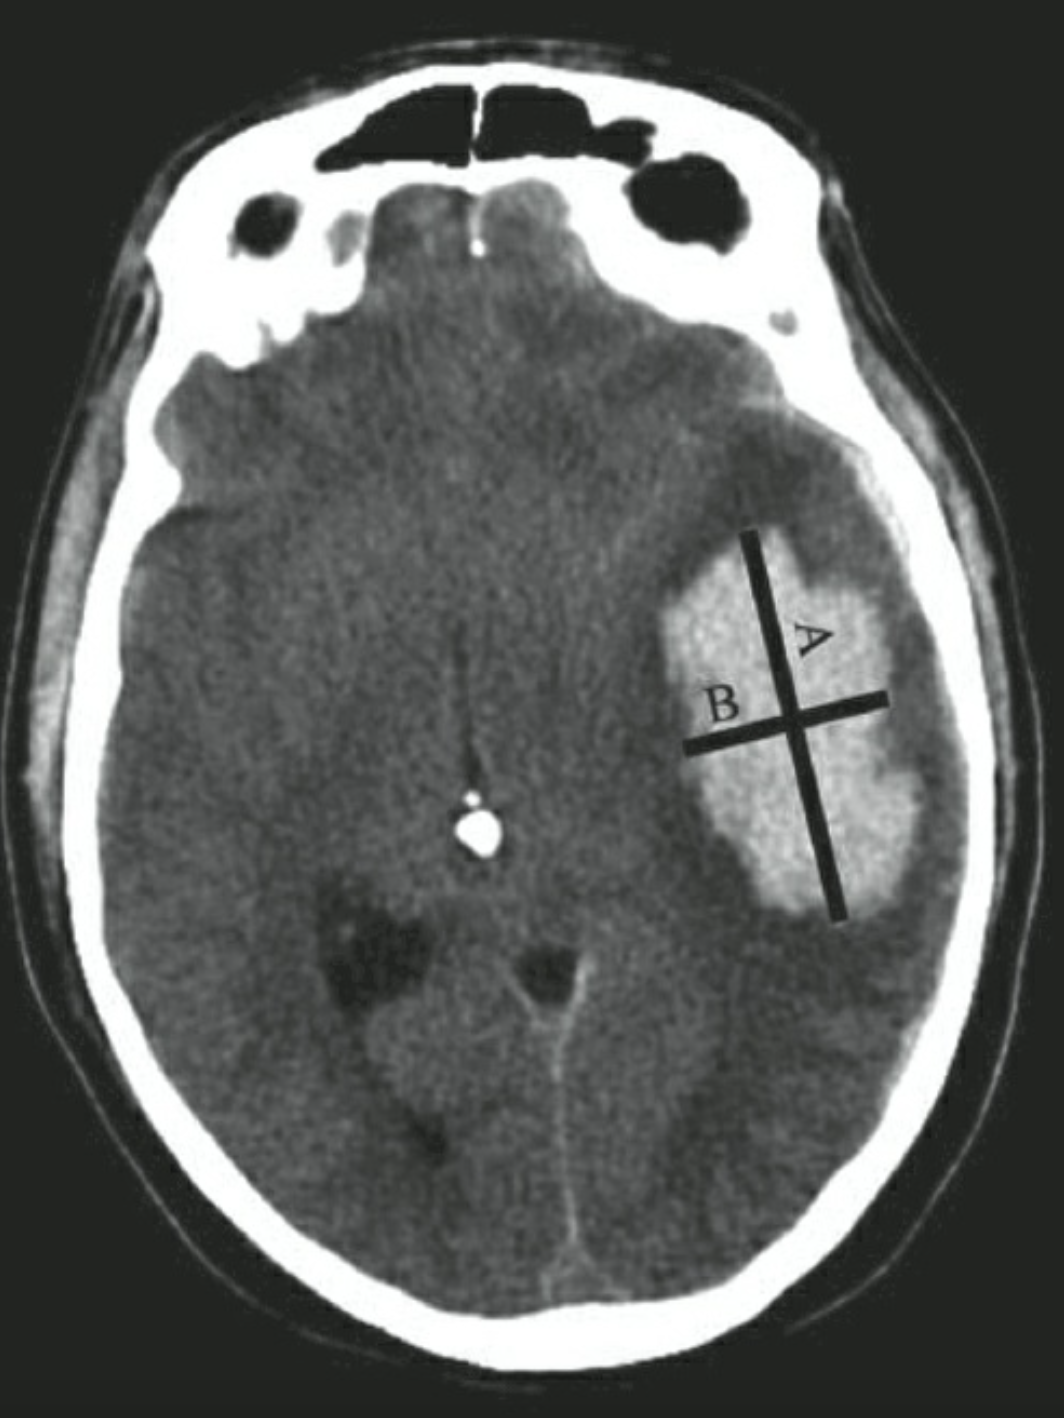

CT sọ não ngoài việc chẩn đoán xác định xuất huyết não, còn cung cấp thêm các thông tin hữu ích khác bao gồm vị trí, lan rộng vào não thất, giãn não thất, sự xuất hiện và mức độ phù não, và sự đè đẩy đường giữa cũng như thân não thứ phát do hiệu ứng khối của khối máu. Thể tích khối máu nội sọ là yếu tố dự báo mạnh mẽ đầu ra lâm sàng của bệnh nhân và có thể xác định được nhanh chóng ở khoa cấp cứu dựa vào kỹ thuật đo ABC/2.

NOTE

- Chọn lát cắt ngang của CT có vùng chảy máu lớn nhất

- Đo đường kính lớn nhất (A) và đường kính vuông góc với nó (B).

- Đường kính C được tính bằng độ dày lát cắt của phim chụp nhân với số lát cắt quan sát thấy khối máu.

- A, B, C được đo theo cm.

- Thể tích khối máu V=ABC/2 có đơn vị cm3 hay mL.